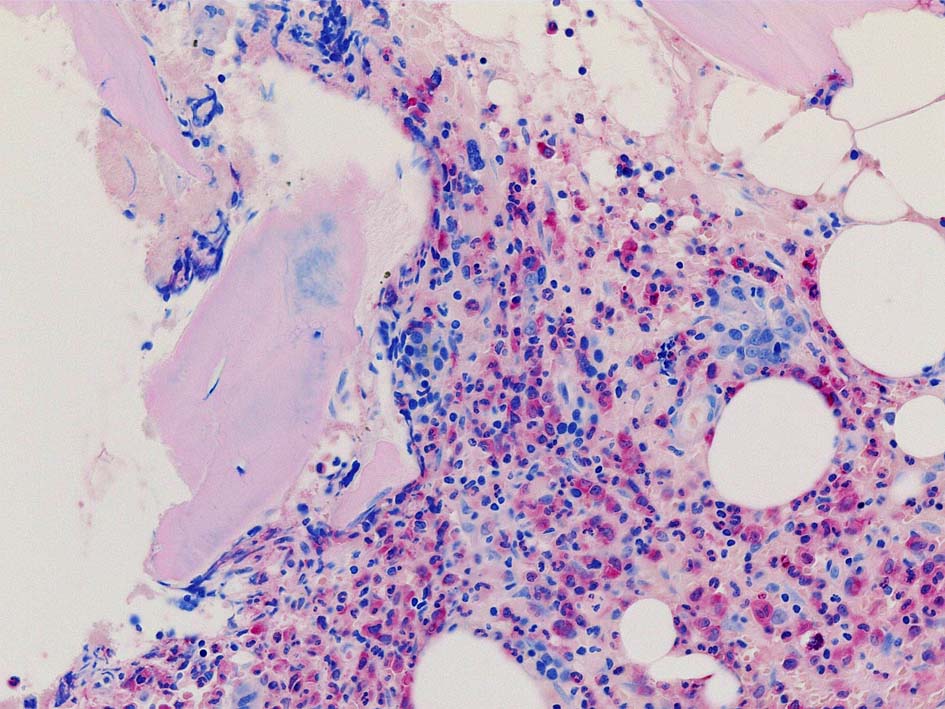

77year-old female. 40歳時polycythemia veraと診断されていた.

[注] この症例は詳細は不明であるが, 過去にPVと診断されているため, PVに伴う二次性のmyelofibrosisの診断になる.

黒染する弾性線維の増生のほか, 赤く染まる膠原線維の増生が確認される. MF-2 fibrosis. 鍍銀染色の核染色をすると膠原線維の赤染がわからなくなるので行わない.